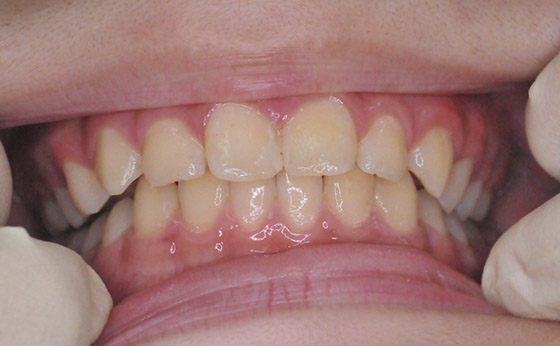

ホワイトニングの症例

症例01

ビフォー

アフター

症例02

この方は毎年、ホワイトニングをして数年、現在もご覧のような綺麗な歯をしております。